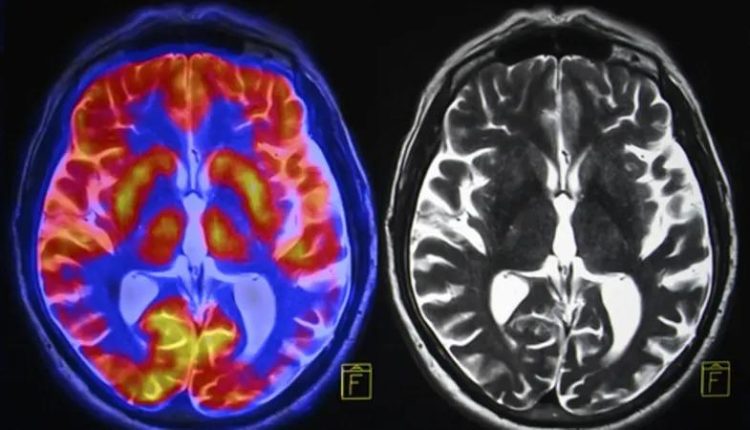

وقارن الباحثون فحوصات التصوير بالرنين المغناطيسي لـ 81 مراهقاً في الولايات المتحدة قبل الوباء، بين نوفمبر 2016 ونوفمبر 2019، مع 82 مراهقاً تم جمعهم بين أكتوبر 2020 ومارس 2022، أثناء الوباء ولكن بعد رفع الإغلاق، بحسب صحيفة “غارديان” البريطانية.

وبعد مطابقة 64 مشاركاً في كل مجموعة لعوامل تشمل العمر والجنس، وجد الفريق أن التغيرات الجسدية في الدماغ التي حدثت خلال فترة المراهقة، مثل ترقق القشرة ونمو الحُصين واللوزة، كانت أكبر في فترة ما بعد الإغلاق، مقارنة بمجموعة ما قبل الجائحة، مما يشير إلى تسريع مثل هذه العمليات. بعبارة أخرى، تقدمت أدمغتهم بشكل أسرع.